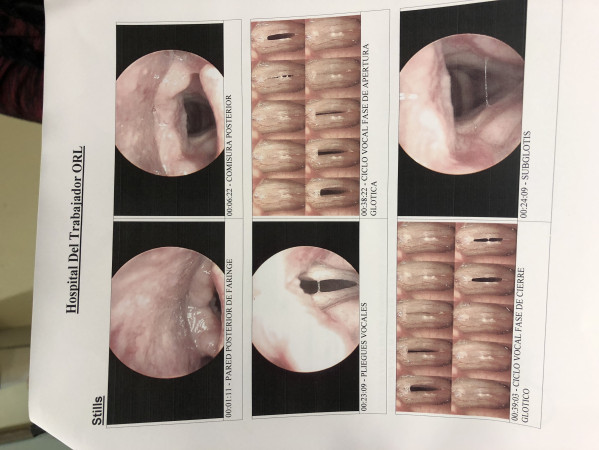

Evaluación, diagnostico y tratamiento fonoaudiológico, para niños, adolescentes, adultos y adultos mayores. habilitación y rehabilitación del habla, lenguaje, voz, deglución. Tratamiento de autismo, síndrome de down, disfagias, TEL, difluencias o tartamudez, cuerdas vocales (nodulos, polipos, parálisis etc), técnica vocal y oratoria para cerrar negocios.